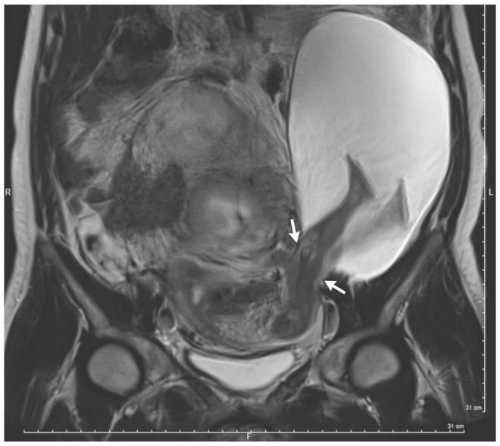

Kết quả chụp phim ở tuần thai thứ 22, một phần túi ối kích thước 19 x 12 x 9 cm bên trong cơ thể người phụ nữ 33 tuổi đã trượt qua lỗ ở thành tử cung. Kết quả, chân thai nhi đạp ra bên ngoài lớp bảo vệ vốn có.

Hình ảnh siêu âm cho thấy chân thai nhi nằm ở ngoài thành tử cung.